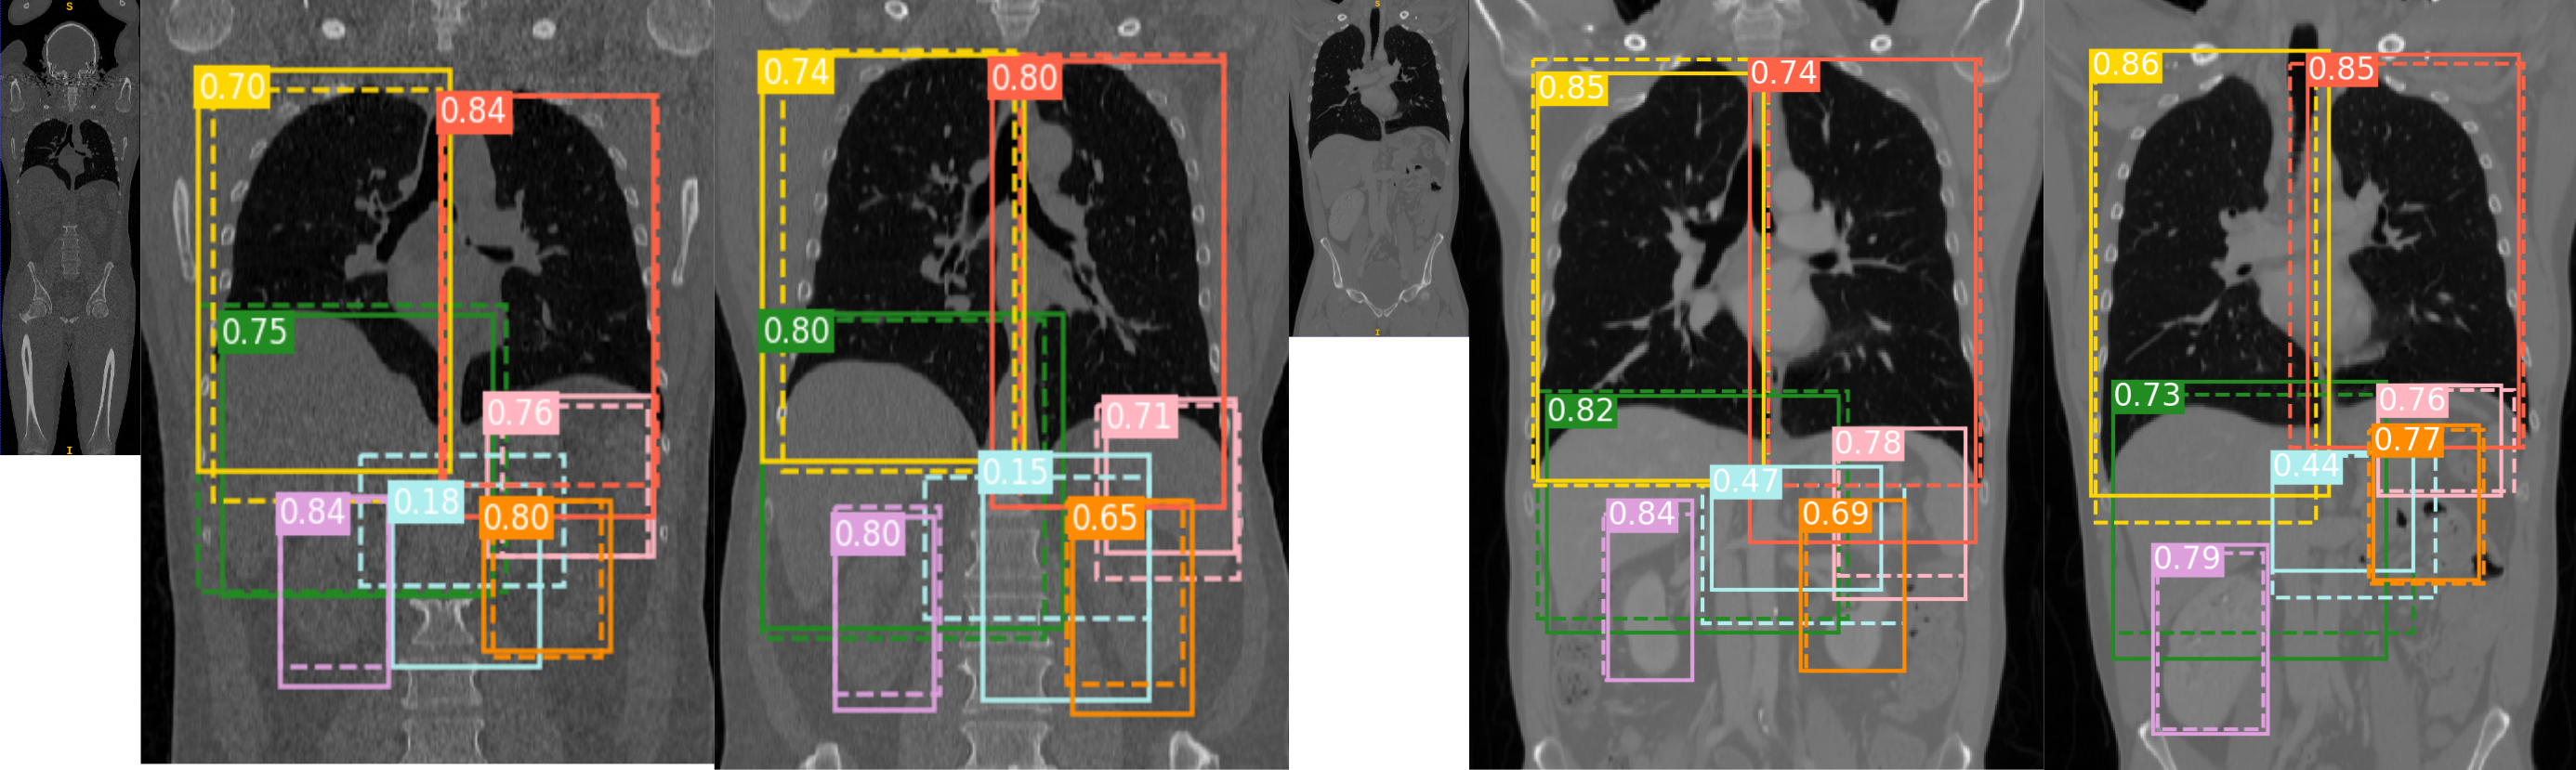

Refer to caption

Figure 3: Qualitative results: Each image shows the mid-slice in the coronal view. For each organ, the dotted lines correspond to the ground truth location, while solid lines denote the agents’ prediction. The small image represents the field of view of the adjacent sample images. The first set of images is whole-body CT without contrast, and the last set of images is thorax ceCT. Each organ’ truth location and network prediction is illustrated with a different color. Liver , right lung , left lung , right kidney , left kidney , spleen , and pancreas . IoU is displayed for every organ. (Visualized better in color)

Visualizing the localization: To qualitatively evaluate the organ localization, Figure 3 shows sample volumes in the testing dataset with its corresponding organ localization. Dotted lines describe the ground truth locations and solid lines the predicted box. Each organ is represented with different color as described in Figure 3. We can observe that the artificial agent is able to localize most of the organs with IoU values between 0.65 to 0.9. In most of the cases the agent either includes all the organ of interest in the prediction, or the predicted box is close to the ground truth. This is a desired property for algorithms that use localization as as a pre-processing step.